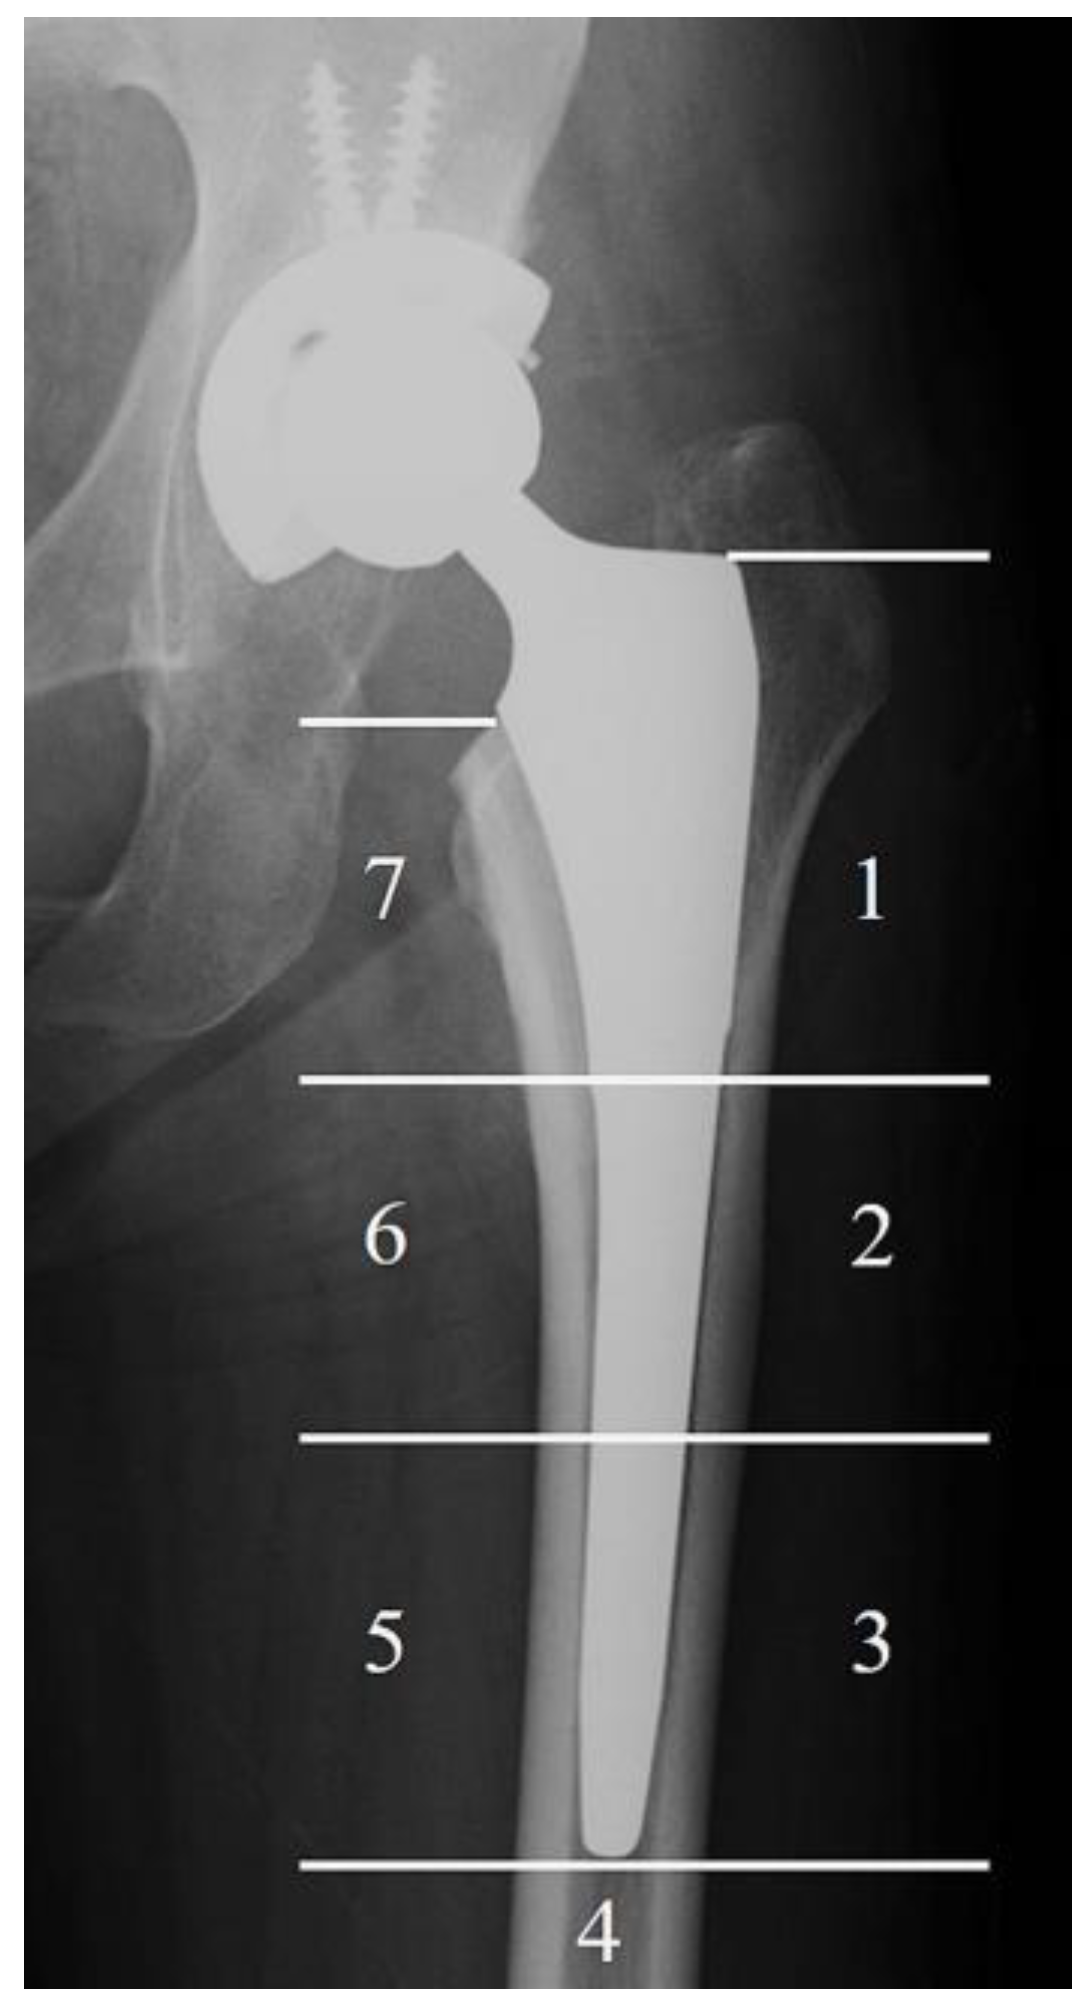

| Gruen Zone | TNS Group | Control Group | p Value |

|---|---|---|---|

| Zone 1, n (%) | 15 (44) | 10 (48) | 1 |

| Zone 2, n (%) | 5 (15) | 9 (43) | 0.02 * |

| Zone 3, n (%) | 0 (0) | 4 (19) | 0.01 * |

| Zone 4, n (%) | 0 (0) | 0 (0) | 1 |

| Zone 5, n (%) | 0 (0) | 1 (5) | 0.38 |

| Zone 6, n (%) | 3 (9) | 11 (52) | 0.001 ** |

| Zone 7, n (%) | 27 (79) | 17 (81) | 1 |